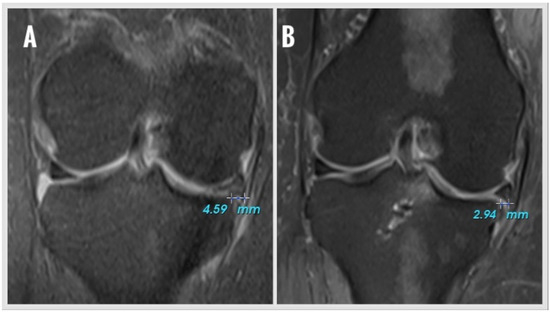

Arthroscopic All-Suture Anchor Repair of Medial Meniscus Posterior Root Tears Without a Posteromedial Portal: Clinical Improvement and Healing Despite Persistent Extrusion

by Murat Aşci, Yavuz Şahbat, Mete Gedikbaş, Utkan Sobay, Fırat Erpala and Taner Güneş

J. Clin. Med. 2025, 14(23), 8272; https://doi.org/10.3390/jcm14238272 - 21 Nov 2025

Background: It is known that meniscus root tears affect the biomechanics of the knee in a way that is equivalent to a total meniscectomy. Therefore, repair is increasingly favored for meniscal root tears. In our study, we aimed to investigate the clinical and radiological outcomes of meniscal root repairs with suture anchors. Materials and Methods: Patients who had undergone surgery for medial meniscus posterior root tear (MMPRT) using suture-anchors between 2018 and 2023 were retrospectively analyzed. Patients were excluded if they had a previous infection, a fracture and an operation on the same knee, or osteoarthritis and a follow-up period under one year. The MMPRTs were classified according to the LaPrade classification system. For the functional classification, the range of motion (ROM), the Visual Analog Scale (VAS), the Lysholm Knee Score (LKS), and the International Knee Documentation Committee (IKDC) Subjective Knee Form were used for the postoperative functional assessments. The radiological assessment was performed by measuring the medial meniscus extrusion (MME) and evaluating the signal changes in the magnetic resonance imaging (MRI) of the knee, which was recorded during the last follow-up examination. Results: Thirty-two patients (6M/26F) were included in the study. The mean age was 49.9 ± 5.4 years old, and the follow-up period was 29.6 ± 24.1 months. The LKS improved from 53.7 ± 6.9 to 83.6 ± 5.2 and the IKDC improved from 46.1 ± 6.9 to 83.0 ± 5.5 at the final follow-up control (p < 0.001 and p < 0.001). The VAS score decreased from 8.4 ± 0.5 to 2.5 ± 0.9 (p < 0.001). The MRI scan of the knee performed at the last follow-up examination showed no improvement in only one patient. While the MME before surgery was 5.0 ± 2.1 mm, it was 4.6 ± 2.1 mm at the last follow-up examination (p = 0.178). An increase in the Kellgren–Lawrence stage was observed in 4 of our patients (from stage 1 to stage 2 in one patient, from stage 0 to stage 1 in 3 patients). Conclusions: The results of this study suggest that repairing MMPRTs using suture-anchors is a valid solution for treatment and prevention in patients with poor prognoses in order to achieve positive results in reducing pain, restoring mobility, improving functional outcomes and avoiding a significant increase in progression to arthrosis. Full article

Show Figures

Figure 1